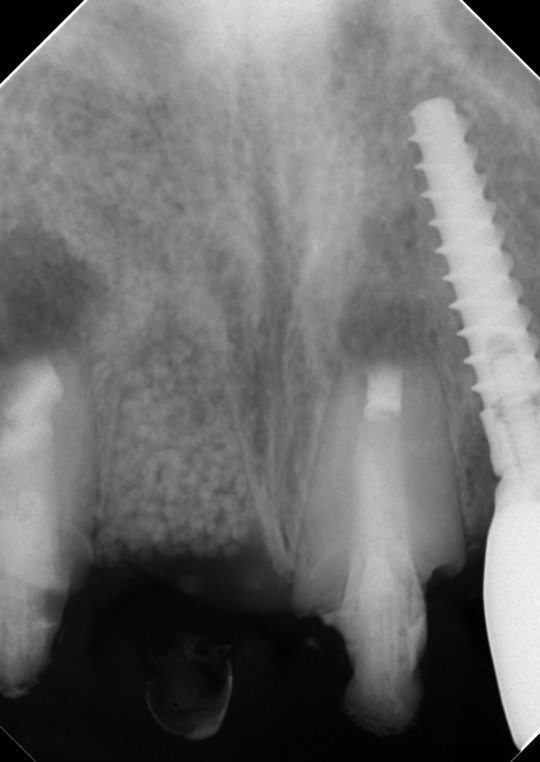

治療後

症状はすべて改善、経過3年後

根の周りが白っぽく骨ができています

骨の穴は完全に消えました